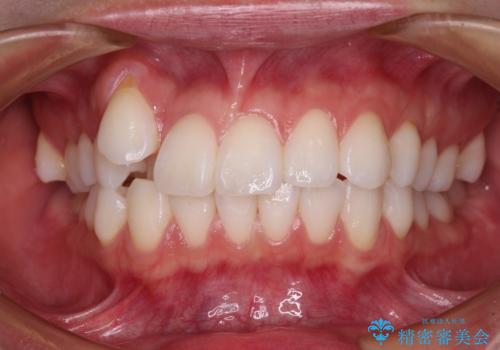

八重歯を矯正治療で治したい!